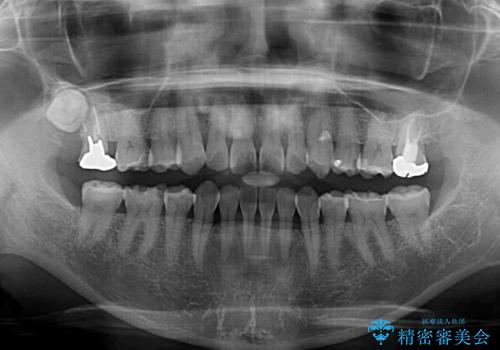

- 下顎前歯を中心に、以前行った矯正治療の後戻りが気になるとのことで来院された患者様です。

後戻りは軽度であったため、インビザライン・ライトにて治療を行うこととしました。

矯正治療後は、再度後戻りすることを極力回避するために、下顎前歯の舌側を細いワイヤーを用いて保定することとしました。